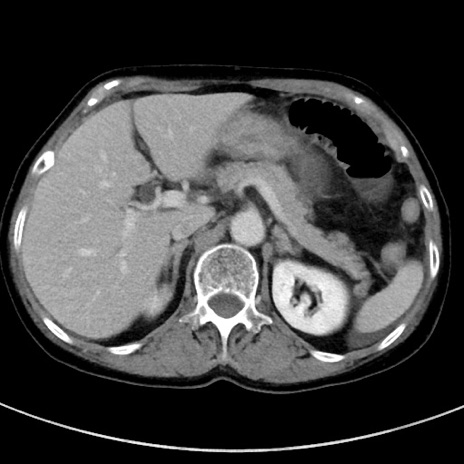

症例23(横断像)

【症例】70歳代女性

【主訴】下腹部痛・嘔吐

【現病歴】2日前より腹痛あり。昨日嘔吐あり。症状改善しないため来院。

【既往歴】胃GISTに対して胃部分切除後。

【身体所見】BT 37.1℃、BP 128/77mmHg、腹部:平坦・軟、下腹部に圧痛あり。

【データ】WBC 10200、CRP 0.31